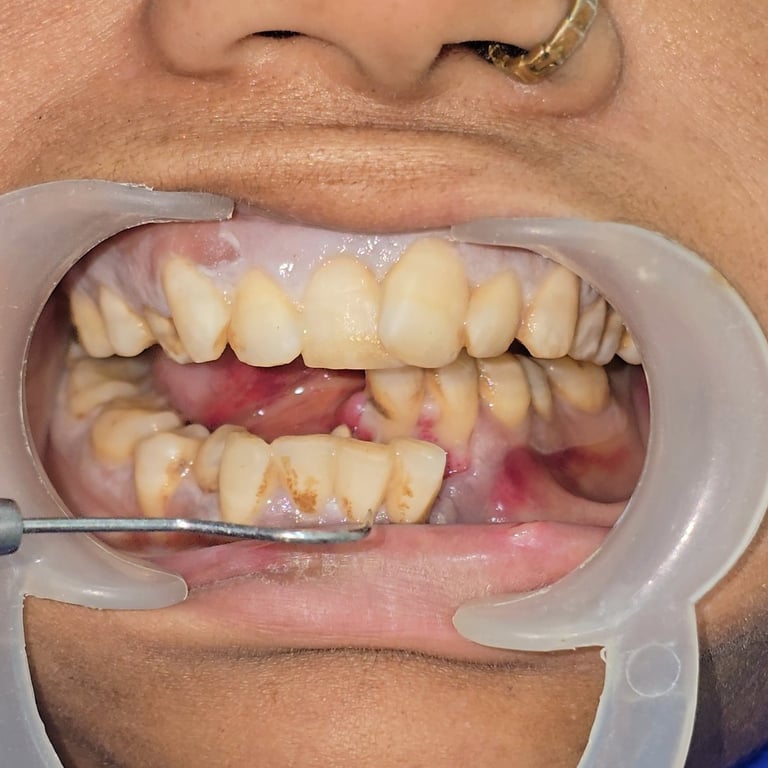

Facial trauma cases involving mandibular fractures are among the most common maxillofacial emergencies seen in dental and surgical practice. A fractured jaw not only causes severe pain and swelling but also affects chewing, speech, and overall facial aesthetics. In this blog, we present a rare case of multiple mandibular fractures in a 40-year-old female patient, including angle fracture, parasymphysis fracture, condylar fracture, and coronoid fracture—all treated successfully with intermaxillary fixation (IMF) and plating.